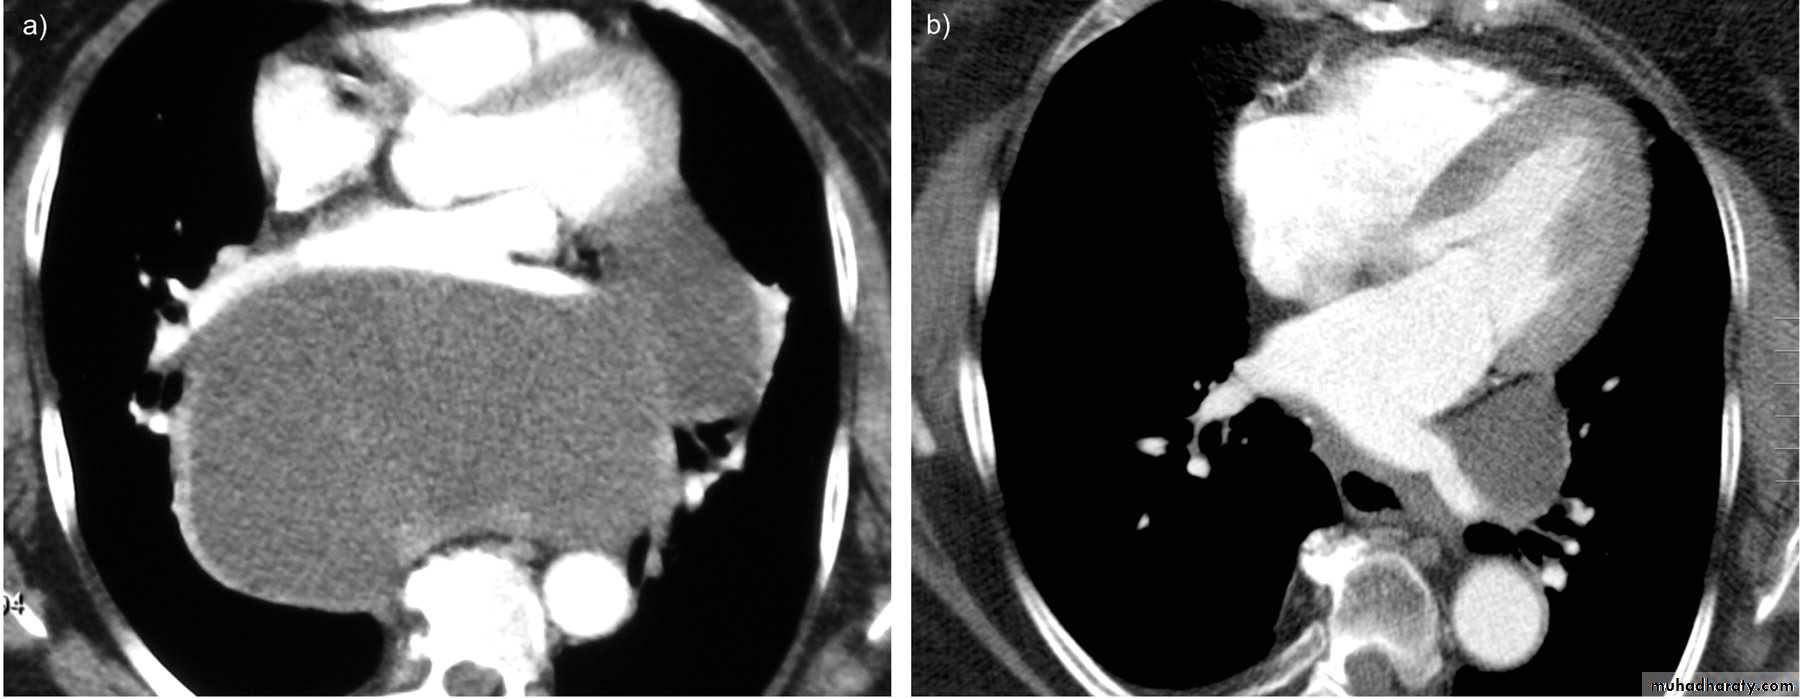

Pericardial cyst

Vascular and chest surgery practical